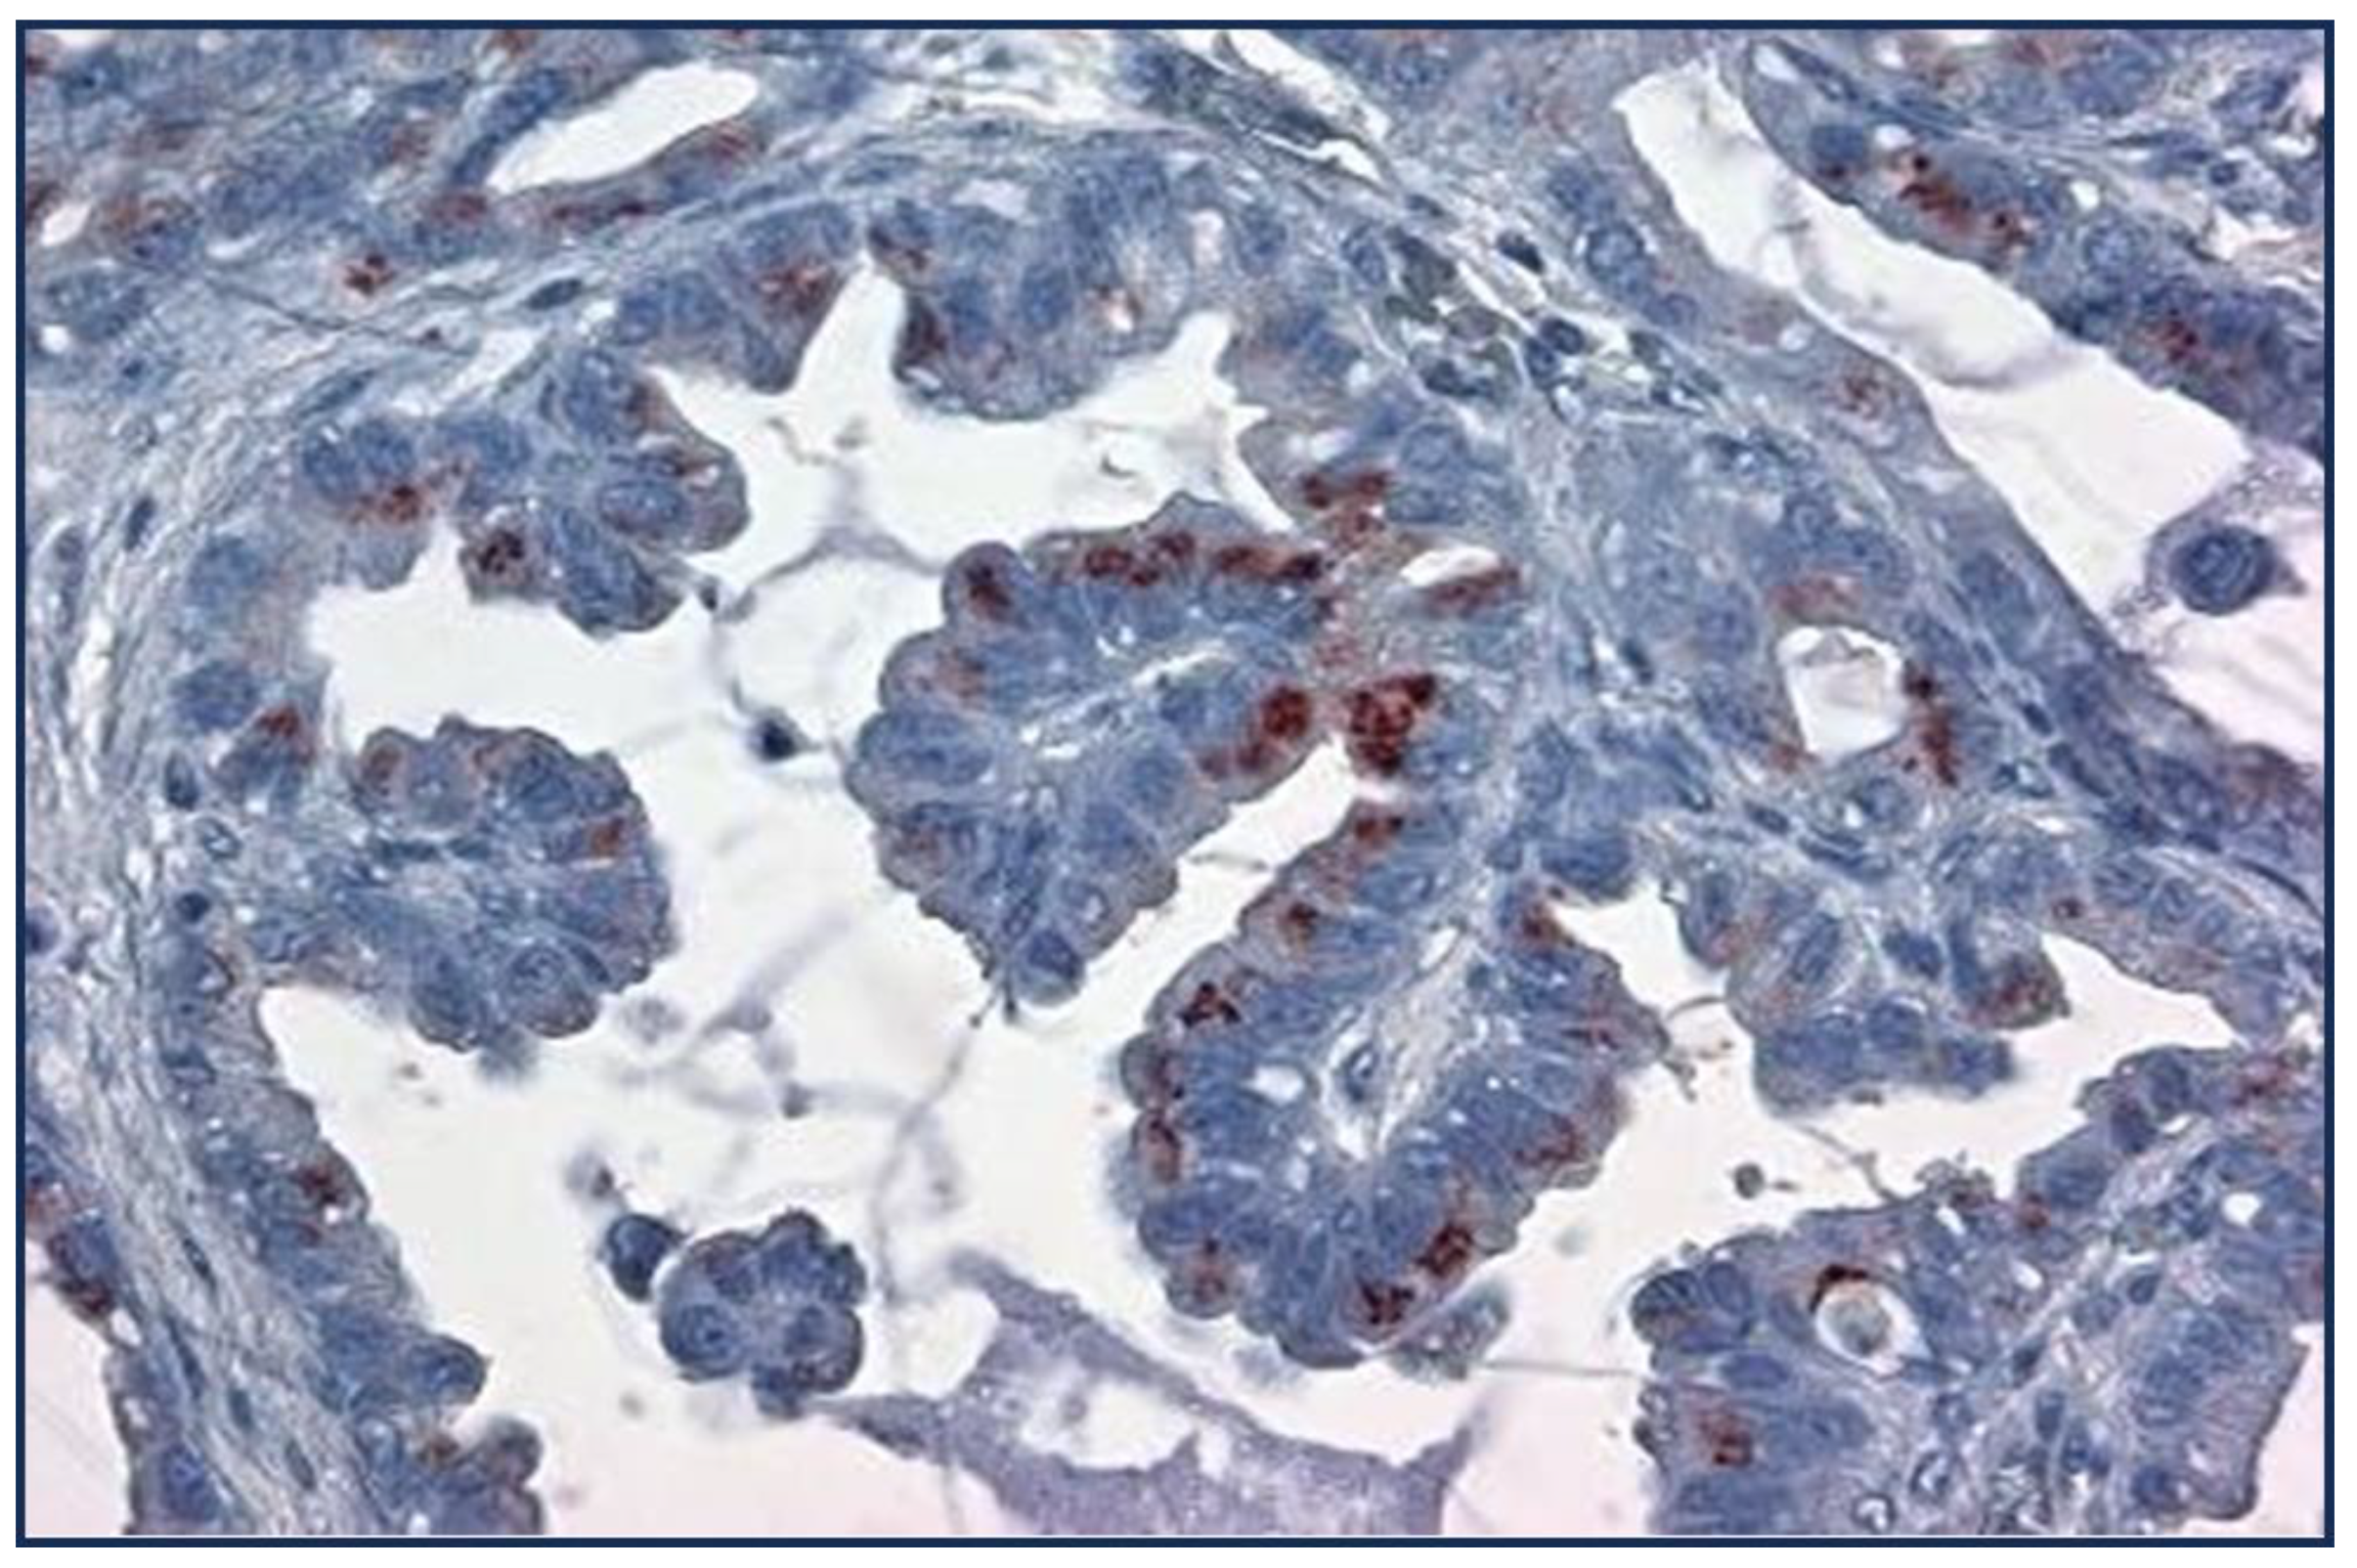

| Cancer Type | Adnab- 9(p87) |

TTF1(Clones) | NE Marker |

%p63/p40 | CK7 (NRecc) |

|---|---|---|---|---|---|

| Lepidic/BA | 67 | N/A | N/A | ||

| AdenoCa | 32 | 80(muc10-15) | N/A | 20-30 | 94-100 |

| Squamous | 6 | N/A | 5-77mean25% | ||

| Large Cell | 0 | 41 (9-85) | 92 | ||

| Small Cell | 22 | 79-100 | |||

| NSCLC | 15 | 10-20 | 68 | ||

| AdenoSquamous | 27 | N/A | 99 | ||

| Papillary | 74 | N/A | |||